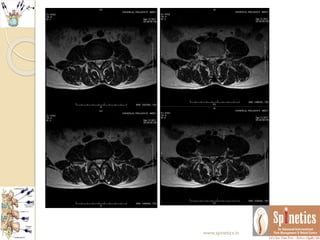

Unusual case

 Neurological behaviour differs in same presenting

spine conditions

 Even though we repeated MRI in one month span as

there is no reccurance what it suggest

 There is resolving annular tear with sequestration

 Many of our patients we routinely found such

herniations which might be too painful to the

patients

 In opposite this patient was not having any

symptoms regarding reccurance of pain

 This the follow-up of more than 2and half years